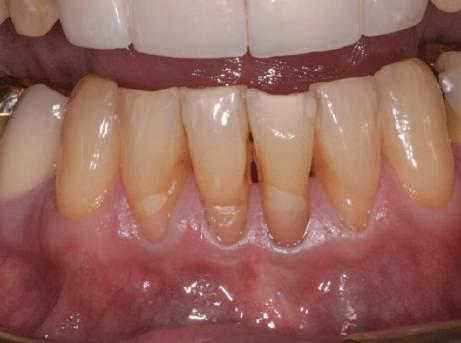

Fig. 1 prezintă pacientul după inserarea primului set de bonturi implantare individualizate; dinţii naturali adiacenţi

sunt încă prezenţi pentru a susţine puntea provizorie.

Şapte luni mai târziu (fig. 2), acele bonturi individualizate din prima etapă au manifestat semne de recesie de 1-3mm. Atitudine: S-a decis reprepararea intraorală a tuturor bonturilor (fig. 3), astfel încât toate marginile bonturilor să fie la nivelul sau sub marginea gingivală (de notat că 1.1. şi 2.1. au fost submersaţi ulterior pentru a avea sprijin implantar deplin).

Deşi reprepararea a îmbunătăţit marcat estetica finală, a necesitat aplicarea şnurului de retracţie, amprente noi şi turnări noi.

Un caz separat dar similar ilustrează în figurile 4 și 5 reprepararea intraorală a bontului.

Cazul (1): Reprepararea intraorală a bonturilor Figurile

1. Aspect după inserarea primului set de bonturi implantare individualizate.

2. După 7 luni, bonturile individualizate din prima etapă au prezentat recesie de 1-3mm.

3. Bonturile repreparate intraoral.

Alt caz (1) Figurile

4. După osteointegrarea implantului 2.4., s-a observat recesia în etapa de amprentare a implantului 2.5.; s-a decis reprepararea marginilor bontului individualizat CAD/CAM 2.4. Înainte de preparare s-a aplicat şnur de retracţie pentru a evita lezarea ţesutului şi a îmbunătăţi vizibilitatea dintelui 2.3. şi a marginii bontului implantar individualizat. Aşa cum era de aşteptat, recesia a fost mai mare de-a lungul versantului distal al bontului 2.4. adiacent locului de extracţie vindecat/cu implantul mai nou.

5. Bontul individualizat aplicat (2.5.) cu bontul repreparat anterior (2.4.). Nu a survenit recesie nouă de o perioadă de peste 3 ani.